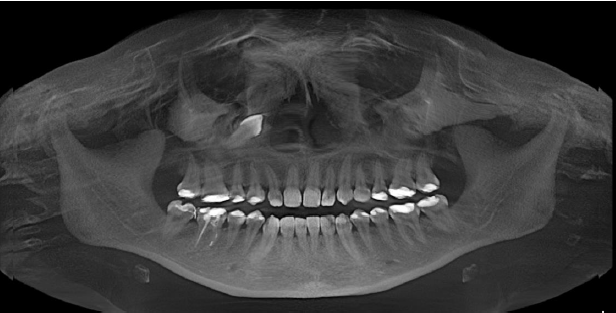

En la exploración intraoral observamos ausencia clínica del canino superior derecho y un diastema entre los dientes 12 y 14 (figura 1). Tras el estudio de la imagen panorámica (figura 2), se observa que el canino derecho superior se encuentra invertido y ubicado en la apófisis ascendente maxilar. Debido a la ubicación ectópica del diente, se solicita una tomografía axial computarizada de la estructura maxilofacial (TAC) (figura 3). Con esta ayuda diagnóstica se tendría mayor información sobre la ubicación exacta del canino derecho superior invertido (diente 13), situado en la apófisis ascendente maxilar, con respecto a las estructuras próximas o cercanas.